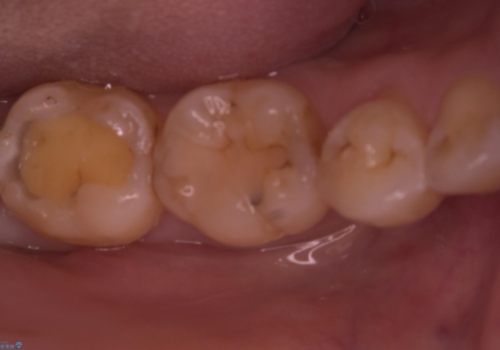

左下7番咬合面にコンポジットレジン修復されてり、経年劣化による着色や歯質との境目にう蝕を認め、セラミックインレーでのやり替えとなりました。

左下7番咬合面にコンポジットレジン修復されてり、経年劣化による着色や歯質との境目にう蝕を認めました。

コンポジットレジンとセラミックの物性的特徴を説明し、セラミックインレーでのやり替えとなりました。